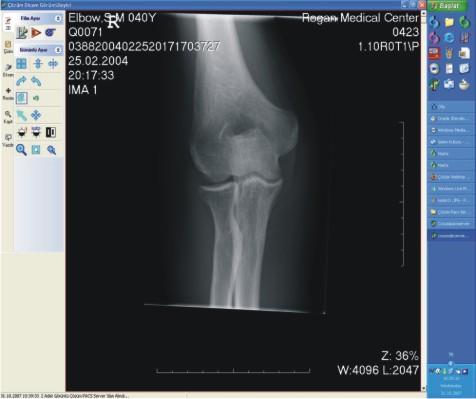

Sayısal görüntüler üzerinde işlem ve ölçüm yapılabiliyor. Görüntüler ve raporların her an, her yerde (tüm iş istasyonları üzerinden sorgulama yapılarak) ulaşılabilir olmasına ve görüntü işleme ve ölçüm (mesafe, açı, uzunluk, yoğunluk) yapılabilmesine olanak sağlıyor.

Kullanıcılar görüntüler üzerinde; diziliş biçimi değiştirme, pencereleme, kenar keskinleştirme, sürekli yakınlaştırma, optik kaydırma, döndürme, aynalama, renkleri ters çevirme, görüntü yazılarını gösterme/kaldırma, Windows'a görüntü aktarma(copypaste), mesafe ve açı ölçümü alma vb işlemleri ayrıayrı gerçekleştirebiliyor.

Radyoloji uzmanlarının tanı süreçlerinin sonuçlanmasında ve doğruluğunda en büyük yardımcı etken Çözüm PACS oluyor [sayısal olarak elde edilen panoromik görüntüler, çözünürlük bozulmadan büyütülüp, belirli bir noktaya odaklanarak, daha detaylı bilgiler elde ediliyor, görüntülerin herhangi bir yerine yazı veya şekil yerleştirmesi ve seçilen görüntünün fare kontrolünde yer değiştirmesi (pan) ve tam ekran incelemesi mümkün oluyor.] İncelenen görüntüler istenildiğinde DICOM yazıcılara gönderilerek film olarak basılabiliyor.

Sayısal görüntülerin ayrı ekranlarda karşılaştırılmasını (yan yana iki çalışma şeklinde, yatay ya da dikey olarak bölünmüş, ters çevirilmiş vb.) sağlayarak, zaman içinde oluşan değişikliklerin değerlendirilmesine, (önceki verilerle karşılaştırma) konsültasyon olanaklarının artırılmasına yardımcı oluyor.